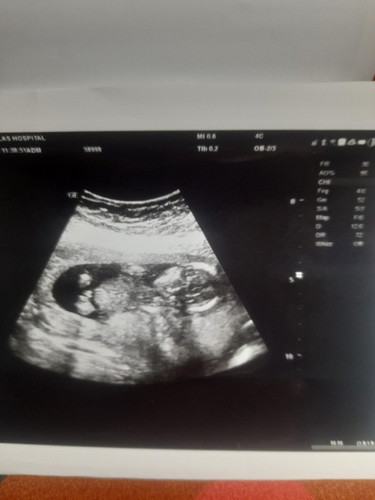

ช่วยดูหน่อยค่ะ น้องเพศอะไร😊 หมอบอกน้องอยู่ในท่านั่งขัดสมาธิค่ะ ดูไม่ชัดเจน หมอเลยบอกน่าจะเพศชายค่ะ

น่าจะมีใข่ค่ะ น่าจะเพศชาย